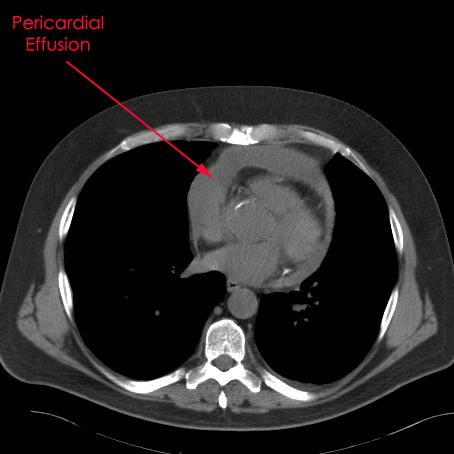

Pericardial effusion - Wikipedia, The Free Encyclopedia

Pericardial effusion ("fluid around the heart") is an abnormal accumulation of fluid in the pericardial cavity. Because of the limited amount of space in the pericardial cavity, fluid accumulation leads to an increased intrapericardial pressure which can negatively affect heart function. ... Read Article